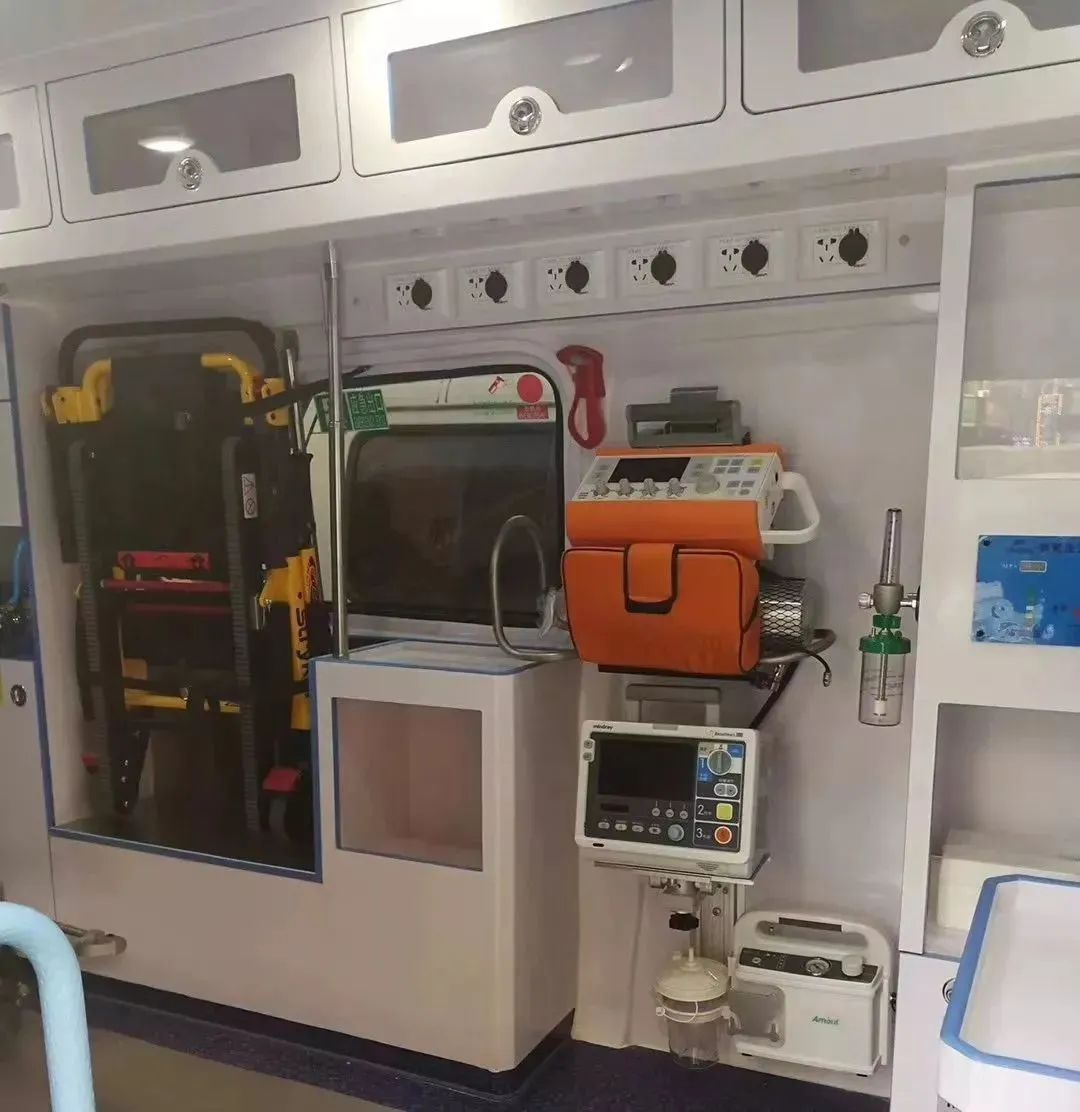

负压救护车

可能很多人不明白,负压救护车是什么,它究竟有何神奇之处呢?

所谓“负压”救护车,我们可以理解为是给普通的救护车带上“口罩”,使车内与车外做到完全“隔离”,此类特种救护车就是专为应对类似此次疫情或突发传染病等情况。

“负压”的关键在于,首先患者所在车内担架上有专门的空气回收口,它会把患者所有呼出的空气全部抽取,经过过滤消毒排出车外。

而车内医疗舱内比外部空气低10-30Pa的大气压,所以车内被污染的空气不会从其他缝隙流出车外,也就不会对周边环境造成污染。

除了负压装置,整车最为关键部位就要属空调系统、空气过滤消毒系统了。按照国家标准,对过滤网的杀菌能力有严格的要求。车内配备了紫外线消毒灯等消毒设备对车内环境进行消毒。

除此之外,负压救护车常见的医疗急救设备也是一应俱全,负压救护车不仅能够隔离病患,常规救护车的清创缝合手术、心肺复苏等抢救都可以在车上进行。